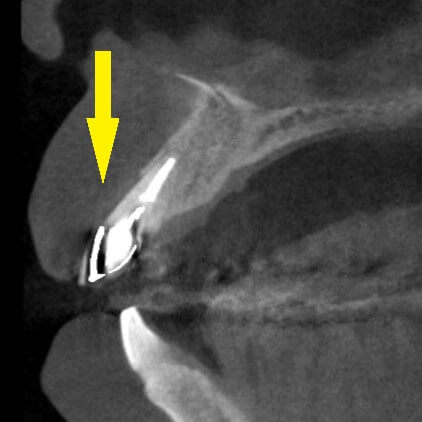

下の写真下段左が、手術前のCT、下段右が手術後のCTです。